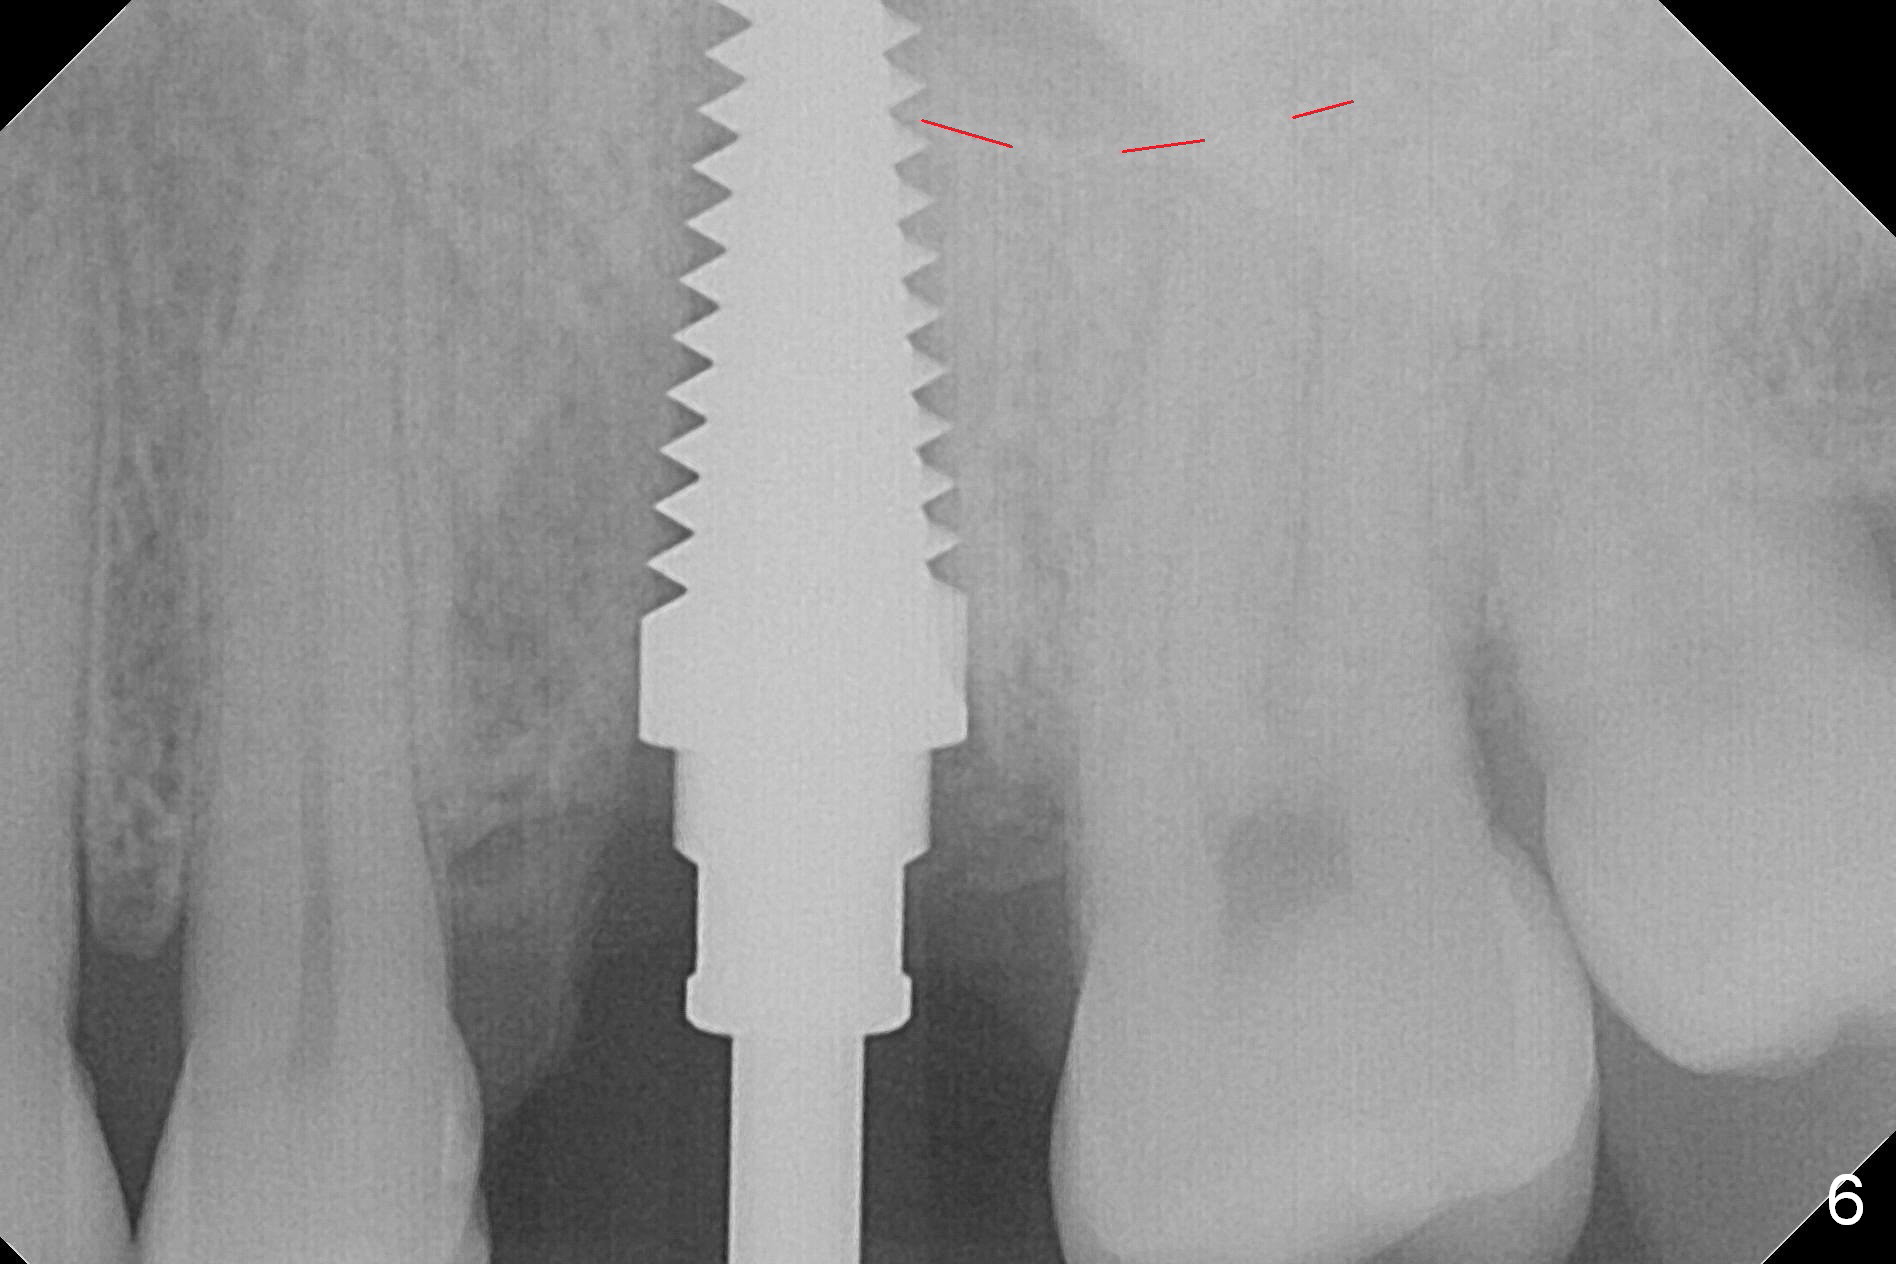

The septum perforates into the distobuccal socket when 4.3 mm drill is being used. The sinus floor bone (Fig.5 *, Fig.6-8 red dashed line) has to be used for primary stability. Finally a 6x20 mm tap achieves stability apparently by engaging to the mesial and distal walls of the socket (Fig.6). The insertion torque of a 6x20 mm tissue-level implant is > 60 Ncm (Fig.7) with allograft packed into the remaining socket (*).